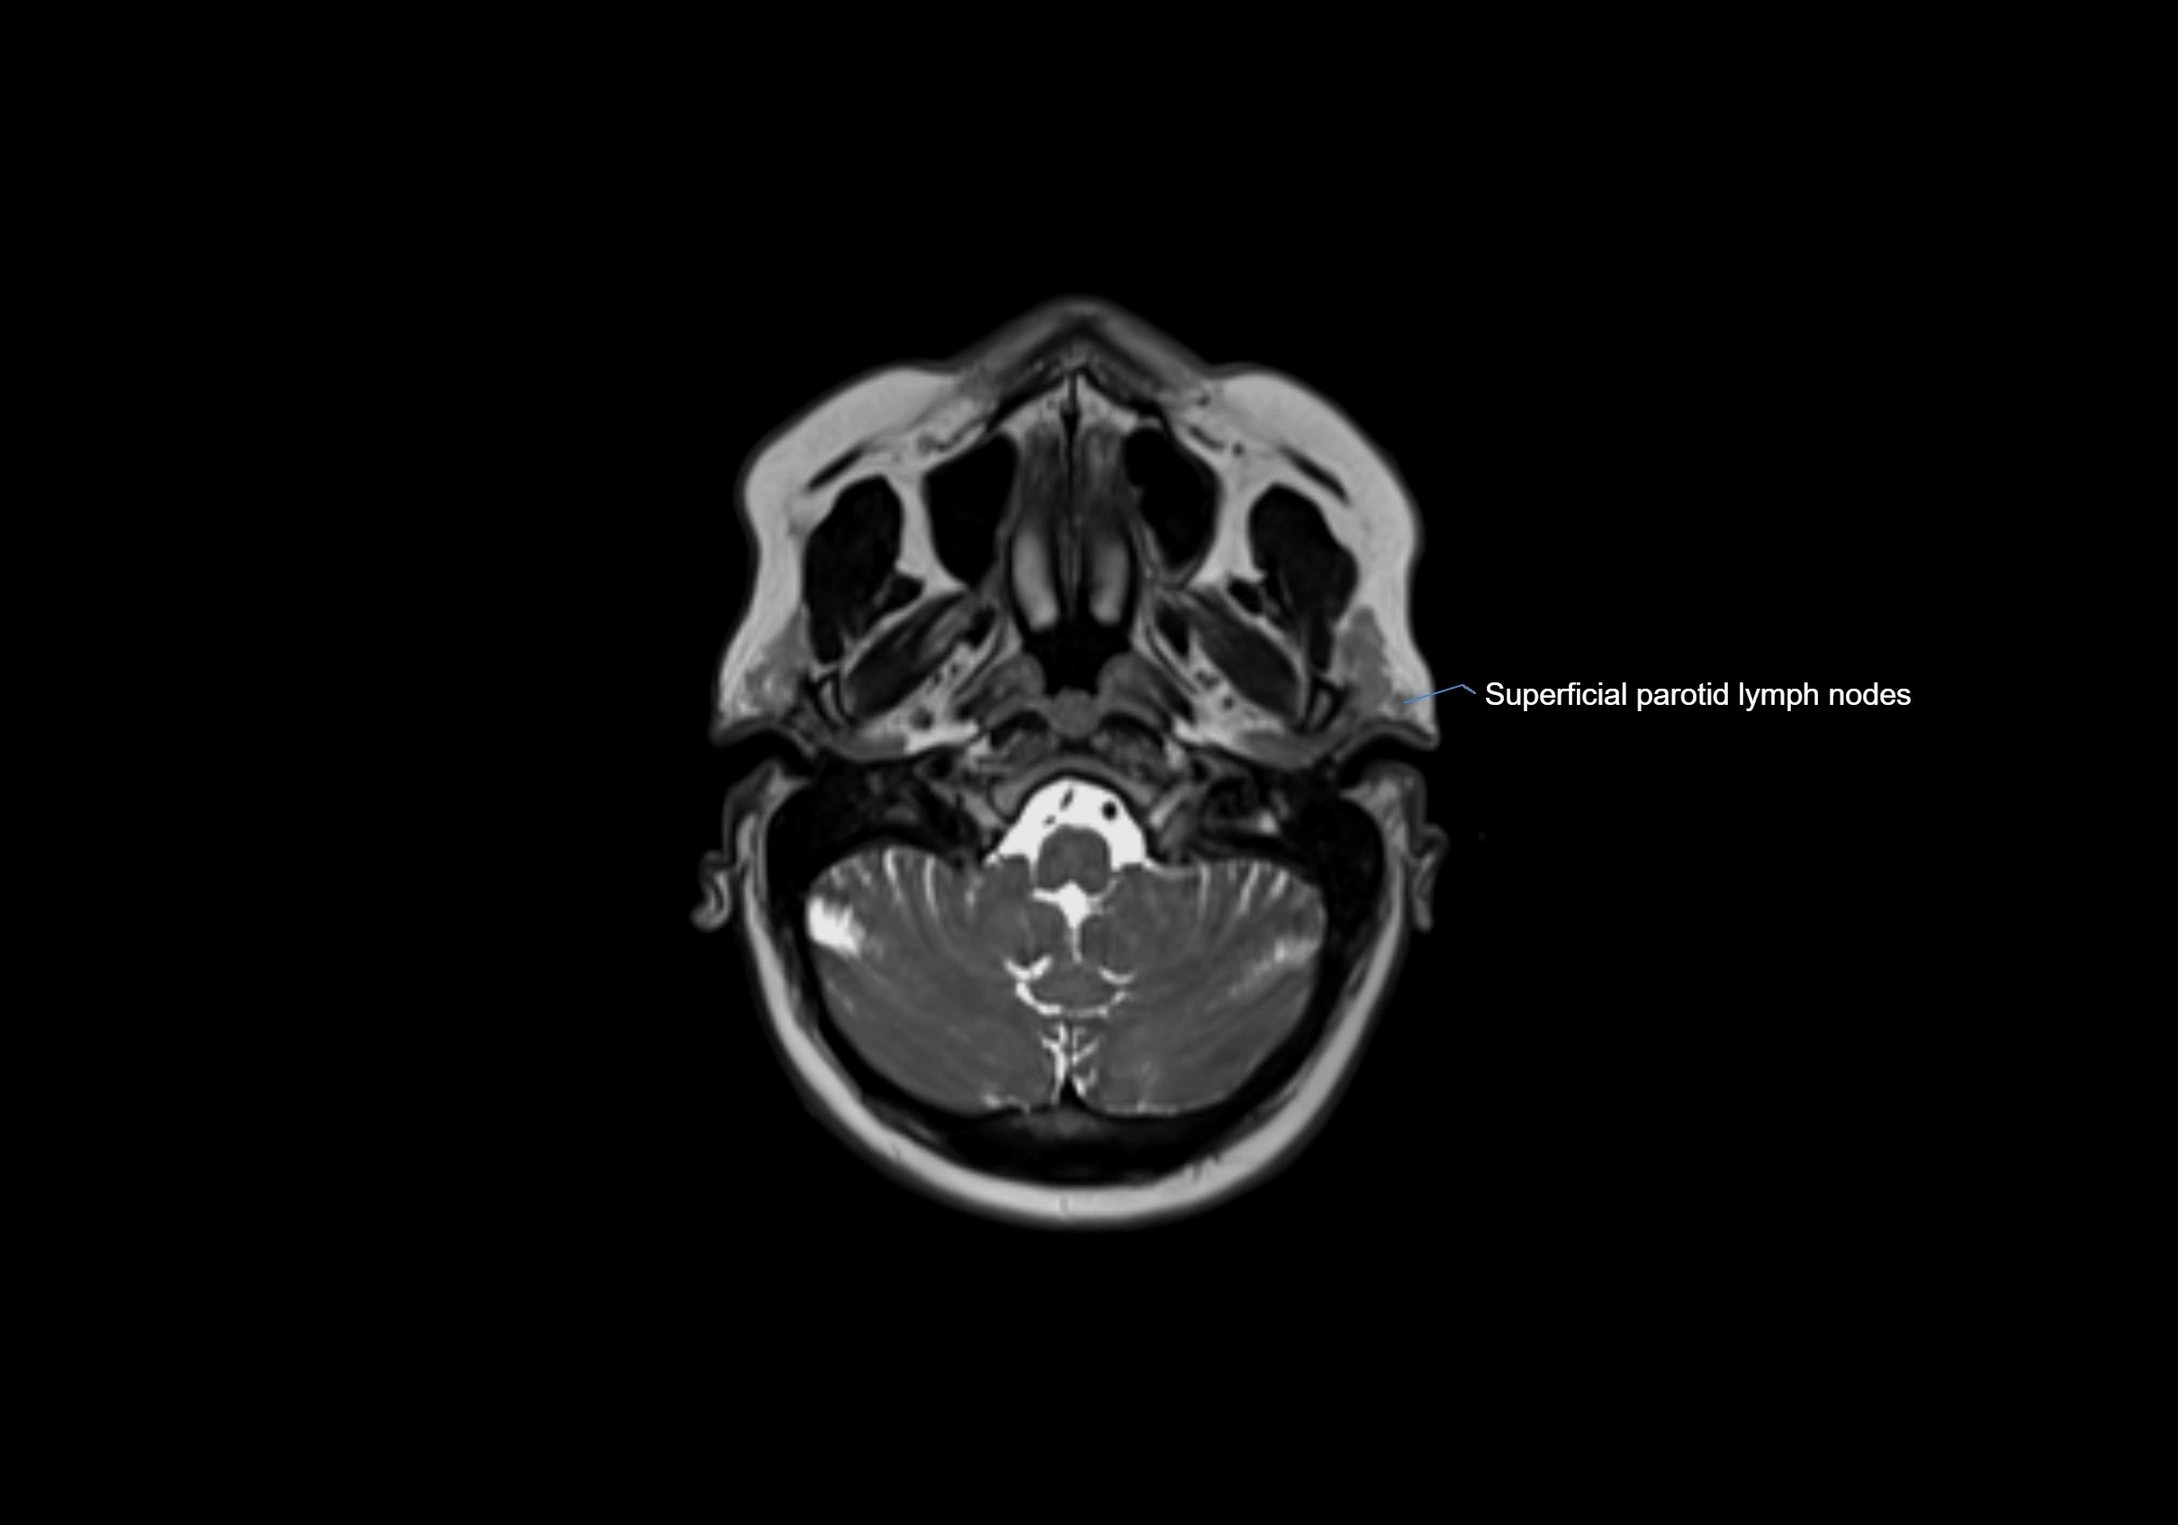

Accessory lymph nodes are small, secondary lymph nodes located along the main facial and cervical lymphatic chains, often adjacent to primary lymph nodes, such as preauricular, submandibular, or occipital nodes. They are typically less than 5 mm in diameter, embedded within subcutaneous fat or connective tissue, and may be variable in number and location. These nodes provide additional filtration and immune surveillance for lymph collected from the face, scalp, and neck regions. Accessory lymph nodes are usually non-palpable in healthy individuals but may enlarge in response to infection, inflammation, or metastasis, making them clinically significant.

Location

• Found along primary lymph node chains, including preauricular, submandibular, parotid, and occipital regions

• Embedded in subcutaneous fat or superficial fascia, often lateral or posterior to primary nodes

MRI images